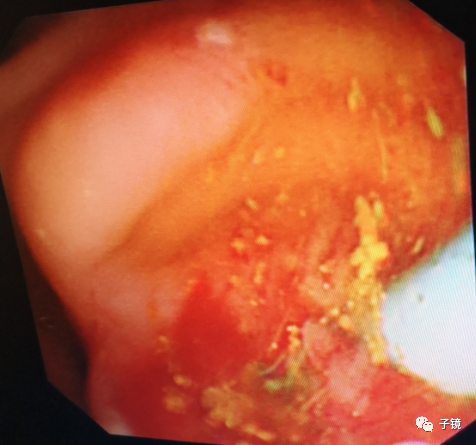

因为镜身固定困难,行乳头切开时调不到最佳的位置,所以进直径10mm球囊扩张导管扩张乳头,扩开后乳头有渗血。

接下来进取石网篮,因为乳头开口血染,不敢贸然进网篮;于是沿导丝“生命线”进取石球囊,在胆总管上段打起来,边造影边往下拖取,感觉结石都拖至胆总管下段了,但拖取不出来。

加力往下拖,看到数个不完整的黄色碎石出来了,应该是结石给予取石球囊压碎了。